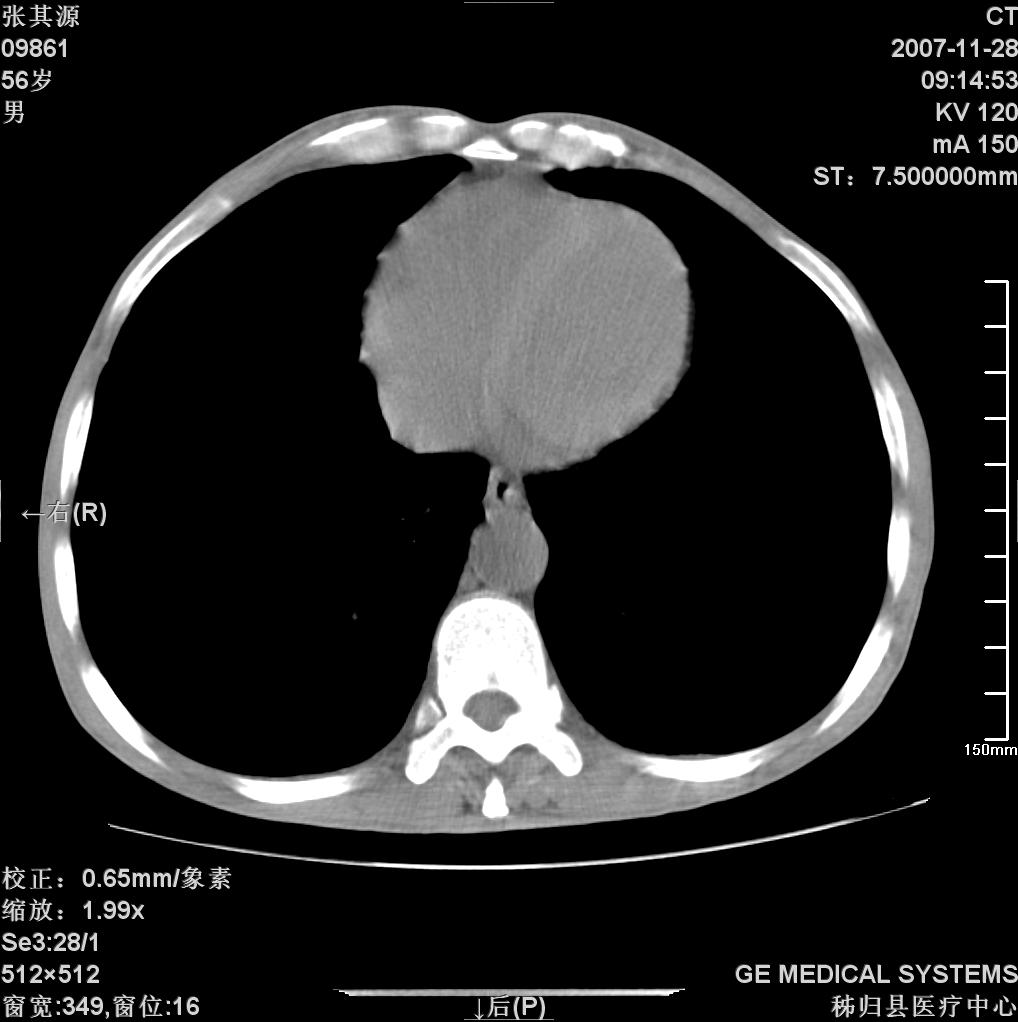

患者因阻塞性黄疸入院,发病前10天持续中等程度发烧.术前检查发现两肺弥漫性病变,请各位大虾会诊,除了考虑急性血源性肺结核外,还有其他什么疾病可能.

双肺多发粟粒样病灶,右肺胸膜下结节样病灶,气管前腔静脉后及隆突下均见肿大淋巴结,结合胆道肿瘤病史首先考虑转移。另外心影密度略低,时间格显示,是否有贫血?查明白再手术吧!